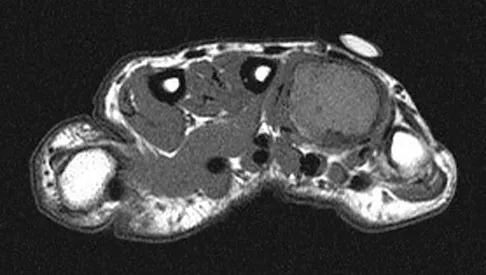

Figures 34a through 34c show an axial proton density (spin echo long TR, short TE) image, a sagittal inversion recovery (STIR) image, and a sagittal T1-weighted (short TR, short TE) image of the left thigh. What is the most likely diagnosis?

Explanation

The images reveal a region of increased signal within the rectus femoris muscle with mild, ill-defined surrounding edema. The presence of high intensity signal on the T1-weighted image favors acute blood, in this case associated with a rectus femoris muscle tear or fatty tissue. However, because of fat suppression, a fatty lesion or lipoma would be dark on STIR, rather than bright as in this image. Most foreign bodies are low intensity signal and if small, are difficult to evaluate with MRI. The lack of adjacent subcutaneous soft-tissue edema or surrounding fluid makes pyomyositis an unlikely diagnosis.